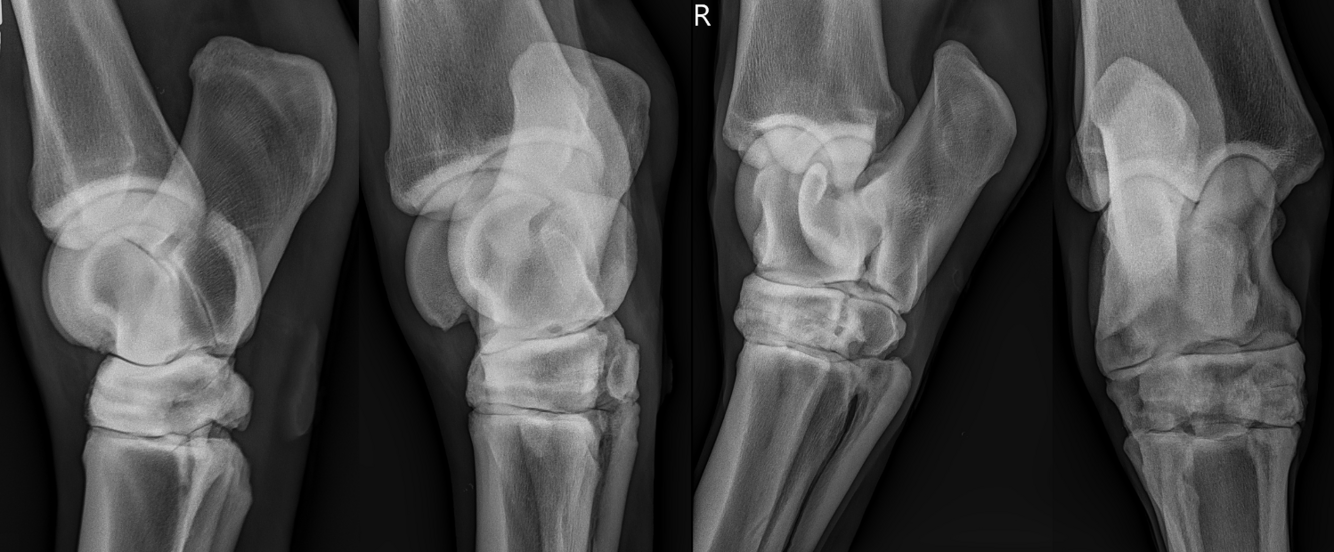

What is shown in these images?

A

tarsal bone collapse; early stage

How well did you know this?

1

Not at all

2

3

4

5

Perfectly

Q

What is shown in this image?

consequences of tarsal bone collapse:

-narrow joint spaces

-abnormal shape of tarsal bones